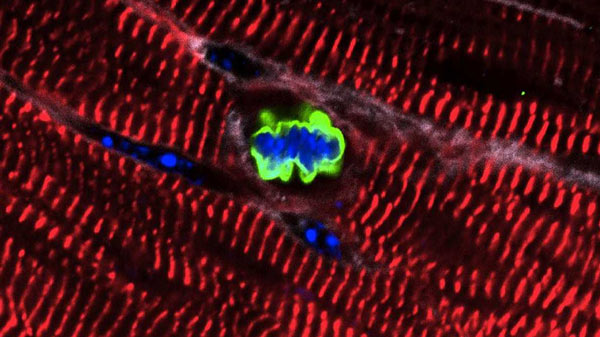

জেব্রাফিশের হার্টের ‘ইসিএম’ (সবুজ)

সহযোগী গবেষক অনাবাসী ভারতীয় পিটস্বার্গ বিশ্ববিদ্যালয়ের বায়ো-ইঞ্জিনিয়ার বাপু হরিশ সালভে ই-মেলে পাঠানো প্রশ্নের জবাবে আনন্দবাজারকে লিখেছেন, ‘‘রং বা বাড়ি-সারাইয়ের সময় আমরা যাকে ‘ভারা বাঁধা’ বলি, বায়ো-ইঞ্জিনিয়ারিং-এর পরিভাষায়, সেটাকেই বলা হয় ‘সেল্যুলার স্ক্যাফোল্ডিং’। আমরা কাজটা করেছি জেব্রাফিশের হার্টের ‘ইসিএম’ বা ‘একস্ট্রা-সেল্যুলার ম্যাট্রিসেস’ নিয়ে। জেব্রাফিশের হার্টের ক্ষয়ে যাওয়া বা পচন ধরে যাওয়া কোষগুলিকে বাতিল করে তার জায়গায় নতুন নতুন তরতাজা কোষ, কলা, অঙ্গ-প্রত্যঙ্গ আপনাআপনিই বানিয়ে ফেলার জন্য এই ‘ইসিএম’ শুধুই বাড়ির ‘ভারা বাঁধা’র কাজটাই করে না, আরও অনেক কিছু করে। ওই ‘ইসিএমে’র ওপর ভর করে জেব্রাফিশের হার্টের নতুন নতুন কোষ, কলা, অঙ্গ-প্রত্যঙ্গগুলি তো গড়ে ও বেড়ে ওঠেই স্বাভাবিক নিয়মে, এমনকী হার্টের অন্যান্য অংশে তাদের ছড়িয়ে পড়তেও সাহায্য করে। এ ছাড়াও তারা সাহায্য করে কোনও নতুন অঙ্গ-প্রত্যঙ্গের জন্ম, বৃদ্ধি, পুনর্জন্মের ক্ষেত্রেও। তাতে দেখেছি, ওই ‘ইসিএম’ যেমন জেব্রাফিশের হার্টে নতুন নতুন কোষ, কলা, অঙ্গ-প্রত্যঙ্গগুলিকে গড়ে ও বাড়িয়ে তুলতে পারে, ঠিক একই ভাবে সেটা নতুন নতুন কোষ, কলা, অঙ্গ-প্রত্যঙ্গ গড়ে ও বাড়িয়ে তুলতে পারে ইঁদুরের হার্টেও। ভয়াবহ হৃদরোগ ‘মায়োকার্ডিয়াল ইনফারকেশন’-এর পরেও ইঁদুরের হার্টে নতুন নতুন কোষ, কলা, অঙ্গ-প্রত্যঙ্গ গড়ে ও বাড়িয়ে তুলতে পারে জেব্রাফিশের এই ‘ইসিএম’। এমনকী, মানুষের হার্টেও এই ‘ইসিএম’ অনেক বৈপ্লবিক ঘটনা ঘটিয়ে দিতে পারে। আমার অবাক হয়ে দেখেছি, তার পরেও ইঁদুরের হার্ট কতটা স্বাভাবিক আচরণ করেছে। যেন কিছুই হয়নি! আমাদের আরও অবাক করেছে জেব্রাফিশের ‘ইসিএমে’র আচার-আচরণ। দেখেছি, জেব্রাফিশের এই ‘ইসিএম’ মানুষের হার্টের ‘মায়োসাইট্স’গুলিকেও (সেই কোষগুলি যা হার্টের পেশিগুলিকে বানায়। এই পেশিগুলিই তো অত্যন্ত চাপ বা আঘাত থেকে বাঁচায় আমাদের হার্টকে) বাঁচিয়ে দিতে পারে। ক্ষয়ে গেলে বা তাতে পচন ধরে গেলে হার্টেই আপনাআপনি ‘রিজেনারেশন’ পদ্ধতির সুইচটা ‘অন’ করে দিতে পারে জেব্রাফিশের ‘ইসিএম’।’’

কলকাতার বিশিষ্ট হৃদরোগ বিশেষজ্ঞ, এসএসকেএম হাসপাতালের কার্ডিওলজি বিভাগের অ্যাসোসিয়েট প্রফেসর অচ্যুত সরকার বলছেন, ‘‘শিশুর জন্মের পর পরই খুব অল্প দিনের মধ্যে মানুষ ‘রিজেনারেশন’-এর ক্ষমতাটা হারিয়ে ফেলে। কিন্তু জেব্রাফিশের মতো নীচের স্তরের প্রাণীদের (মাছ) ক্ষেত্রে হার্টের এই ‘রিজেনারেশন’-এর ক্ষমতাটা থাকে আজীবনই। আর তা জেব্রাফিশের হার্টের অন্তত ৫০ শতাংশ অসুখবিসুখ আপনাআপনিই সারিয়ে তুলতে পারে। আর এই স্বাভাবিক ‘চিকিৎসা পদ্ধতি’ জেব্রাফিশের হার্টকে একেবারে আগের মতোই সুস্থ, সবল করে তুলতে পারে মাত্র সপ্তাহ খানেকের মধ্যে। কোনও কোনও ক্ষেত্রে মাত্র দু’-তিন দিনেই।

সহযোগী গবেষক অনাবাসী ভারতীয় বায়ো-ইঞ্জিনিয়ার বাপু হরিশ সালভে তাঁর ই-মেল জবাবে লিখেছেন, ‘‘জেব্রাফিশের ‘ইসিএম’টাও গড়ে ওঠে কোলাজেন, ইলাস্টিন আর কার্বোহাইড্রেট দিয়ে। আর তার বাইরের স্তরেও এমন কিছু সংকেত থাকে না, যা দিয়ে স্তন্যপায়ীদের কোষ, কলাগুলি বুঝতে পারে, এটা ‘বহিরাগত’! সেখানেই কেল্লা ফতে!’’